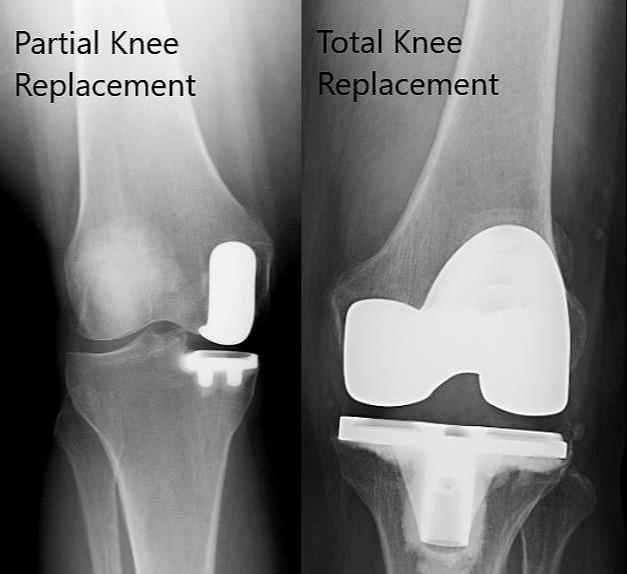

那么如何才能帮助患者解决这个问题呢?膝关节置换手术就被发明出来了。既然这些疾病导致患者的关节软骨被侵蚀掉了,关节变得狭窄,那么想办法把严重增生的骨贅切除,已经被磨损殆尽的关节换成跟原来一样的光滑的关节就好了!这就有点像是我们给牙换牙套,是一个过程。大家看下图就会明白这个过程了。

图片

大家看下面这个动图,可能会觉得这个手术非常的简单,但这是模拟的动图,实际的手术操作非常复杂,要在膝关节的前方切一个纵行的切口,逐层的切开皮肤、皮下脂肪、筋膜、肌肉,进入关节囊,这个创伤是比较大的。之后要将影响关节功能比较多的骨赘,也就是骨质增生切除掉,再使用专用的模具逐渐修整关节的表面,最后替换上假体,之后等待假体固定坚固以后,反复的清洗关节腔,再逐层的将切口缝上。